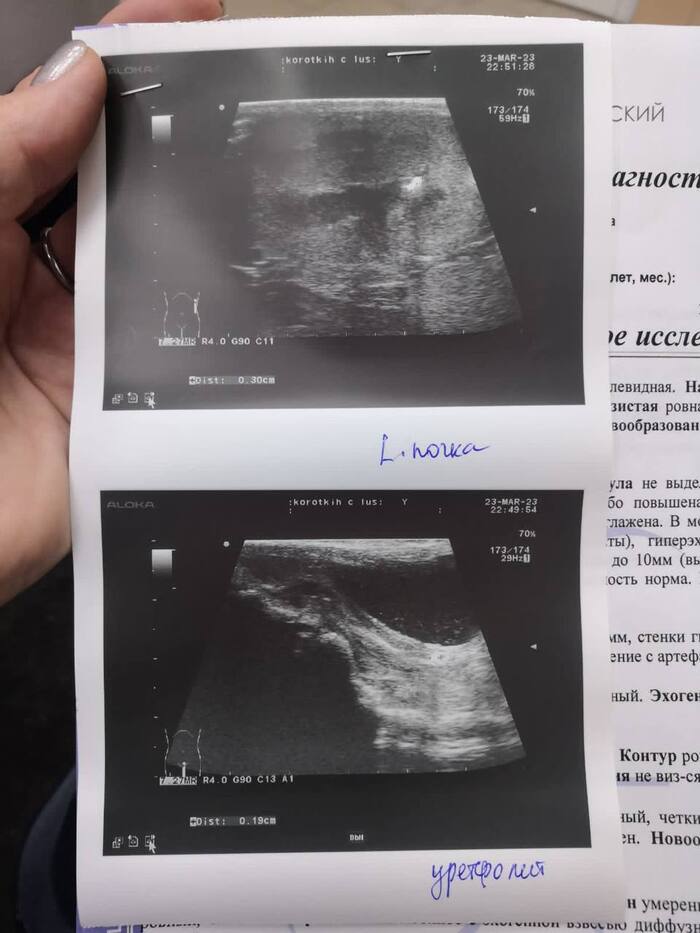

Отказ от еды, угнетенное состояние, обезвоживание. По УЗИ и анализам крови -

нефропатия с потерей белка. Признаки пиелонефрита. Камень в левой почке. Резкий болевой синдром. Прогноз осторожный.